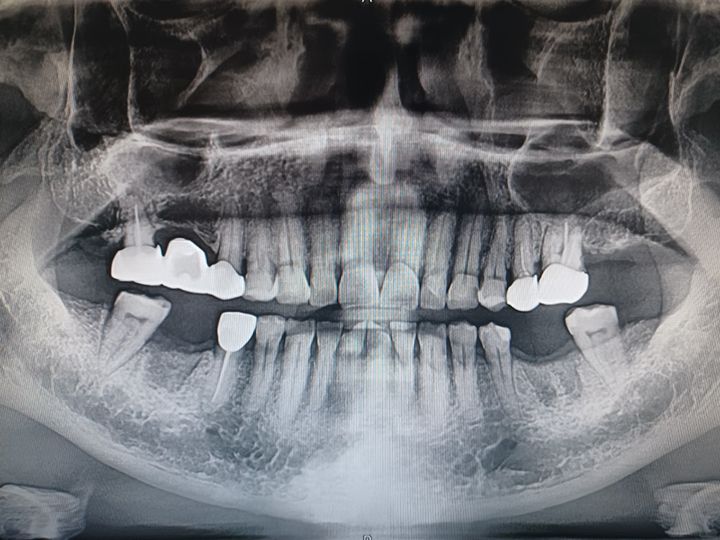

ハル歯科医院は、最先端のインプラント歯科治療に特化したクリニックです。代表のジョー・ハング院長は日本の神奈川歯科大学を卒業し、両国での歯科医師免許を保持。さらに、韓国で専門医資格を取得し、口腔外科など高度な手術経験も豊富です。すべての治療を院長自らが行う専任診療制を採用しており、流暢な日本語で対応可能。「デジタルインプラント」や「無削除ラミネート」などの最新のデジタル歯科治療を、日本の約半額で受けられます。仁川・金浦空港から乗り換えなしで行ける孔徳(コンドッ)駅すぐとアクセスも良好で、旅行者にも便利な立地となっています。

インプラント

匿名さん

日本でインプラント施術を行う予定でいましたが、色々と調べた結果、価格面でこちらで行うことを決めました。

先生との会話も日本語で行えて、海外で施術を受けるという当初の不安は無くなりました。

施術の内容や予算も相談して決められたので安心できました。また継続して訪問させていただこうと思います。

日本からインプラントをしにきました

日本のインプラントは高額なのでネットで韓国の歯科医院を探してました 日本語対応の歯科医はいくつかありましたが せつ術医師に直接日本語で話せるということでハル歯科医院を選びました 先生はとても親切で最初の説明からわかりやすく こちらの質問にも全て親切に答えていただきました 5本のインプラントをいちどに入れていただいたのですが とてもスムーズに5本入れることができました 費用もkonest やホームページに書いてあるとおりで 1本140万wから120万wにディスカウントしてもらい レートも一円 10w で計算していただきました 3ヶ月後にまた来院します この歯科医院を選んで良かったと思ってます